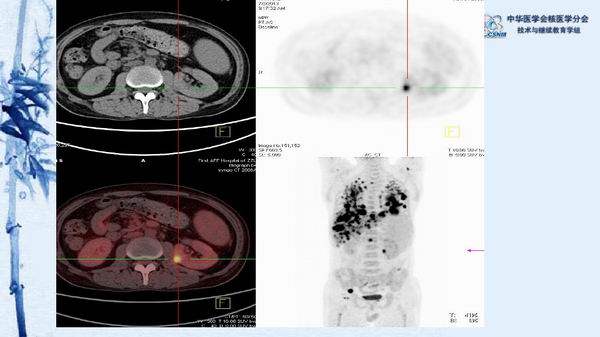

病例49:PET-CT显像诊断淋巴瘤相关噬血细胞综合征一例-【CSNM继教学组】程兵 郑州大学第一附属医院